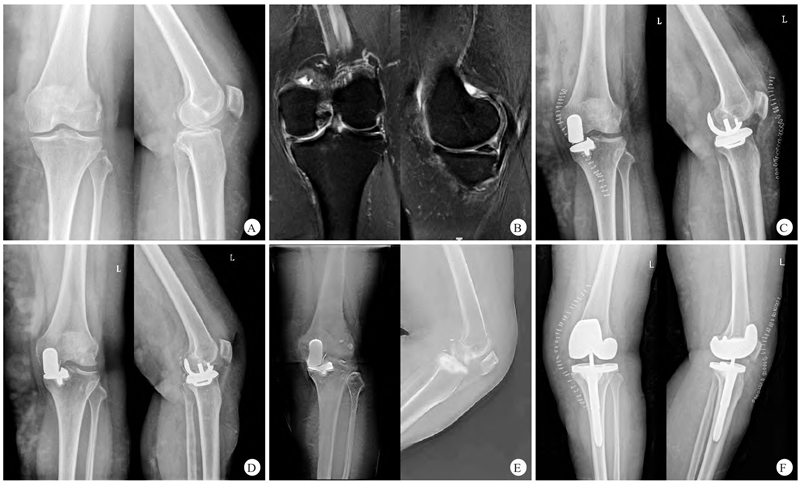

典型病例:图2 患者,女,60岁,左膝单间室骨关节炎,行活动平台UKA

A.术前左膝正、侧位X线片显示内侧间隙变窄;B.术前左膝MRI提示左膝关节退行性病变,内侧软骨磨损;C.术后1周左膝正、侧位X线片显示假体位置良好;D.术后12个月后因外伤摔倒后出现左膝关节疼痛,左膝正、侧位X线片可见衬垫向后外方脱位;E.术后12个月左膝矢状位及冠状位数字化体层融合成像提示衬垫向后外方脱位;F.全膝关节置换翻修术后2周左膝正、侧位X线片显示假体位置良好